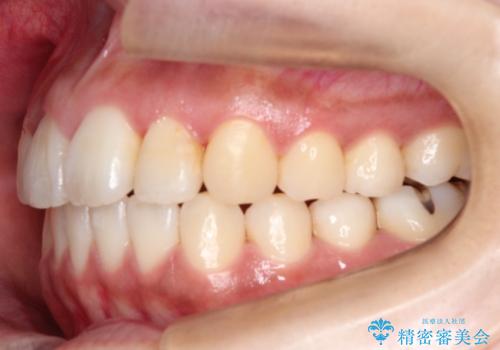

初診時の歯並びの状態としては、上下ともに全体に及ぶの中等度のがたつき(叢生)があり、全特に左上の前歯は1本だけ引っ込んでいる状態でした。

抜歯は行わず上顎の奥のスペースを利用して歯をスライドする方法の他に歯列弓の拡大やディスキング(歯と歯の間の隙間を作る処置)を行い叢生を改善しました。

歯の大きさの不揃いが原因の正中のズレは、ディスキング量を調整することで合わせました。

見た目、嚙み合わせ及び、治療期間や施術内容に大変ご満足いただきました。